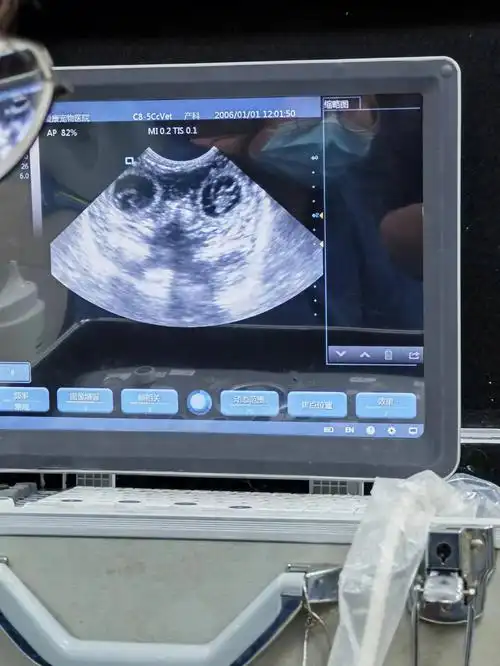

带狗子做孕检的当天发现自己也怀孕了,到医院检查说是大概30天左右了

家里的柯基公主怀孕30天了